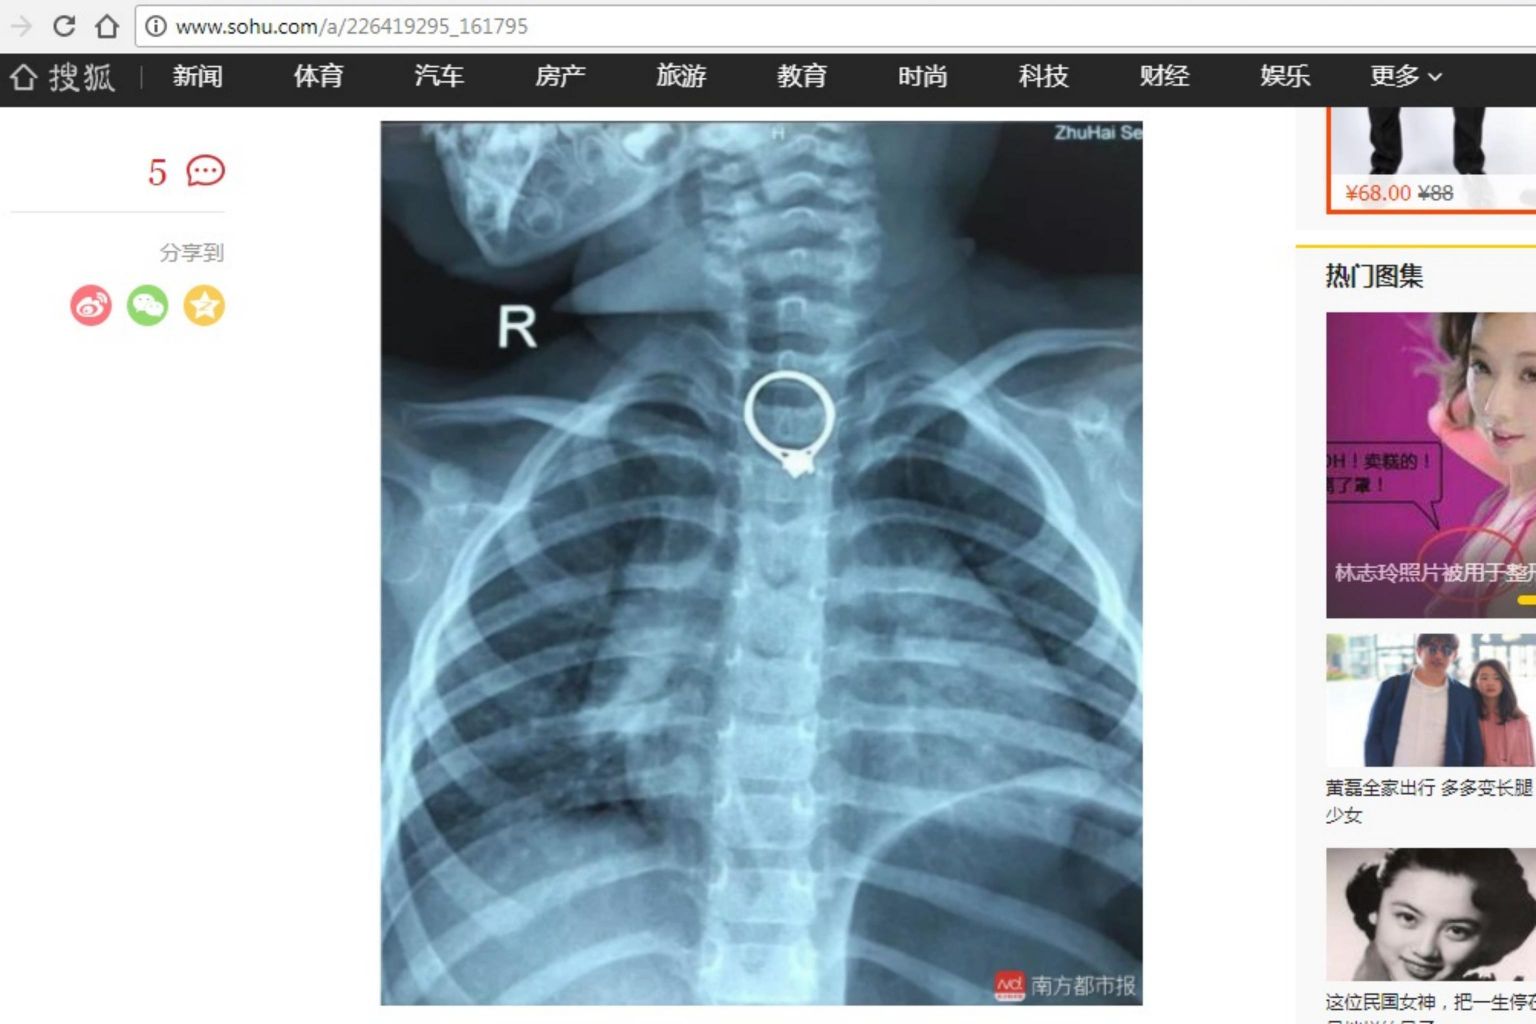

A two-year-old girl was rushed to hospital after swallowing her mother's ring in China's Guangdong province on March 23, 2018.

PHOTO: SCREENGRAB FROM SOHU/SOUTHERN METROPOLIS DAILY

She was rushed to the Zhuhai Hospital of Integrated Traditional Chinese and Western Medicine, where doctors retrieved a diamond ring that measured 2.35cm by 2.05cm from her throat after an operation that lasted half an hour.